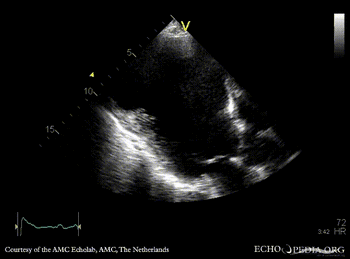

Large aneurysm of LV

PSAX: dilated left ventricle, poor function